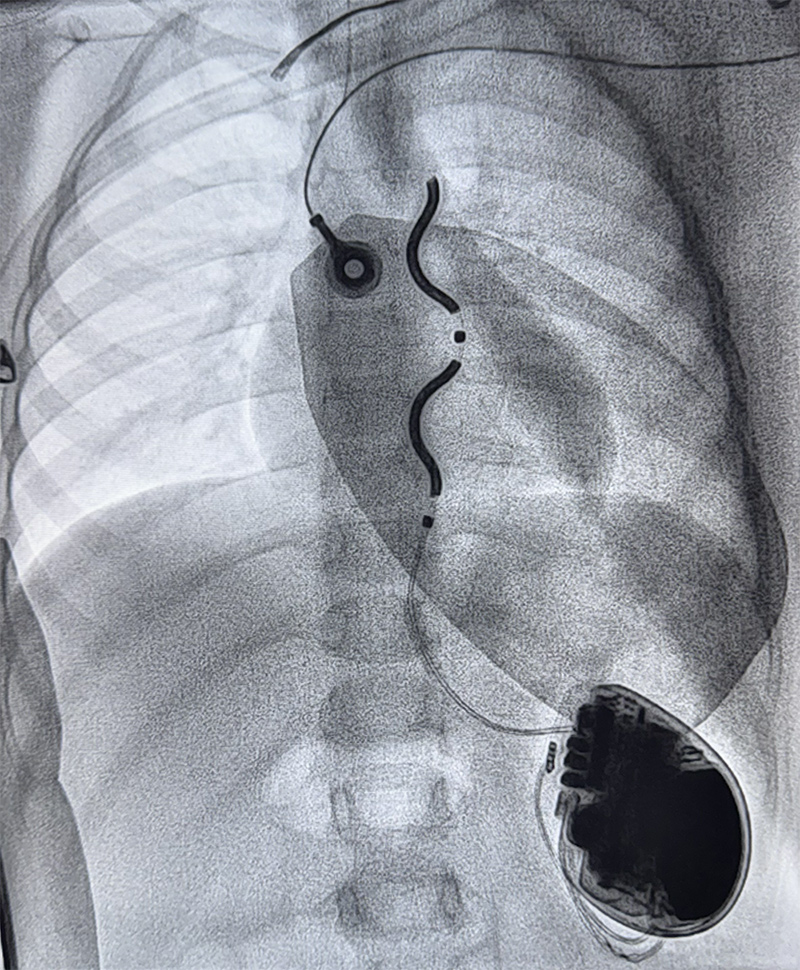

🚀 Première implantation hybride d’un défibrillateur EV-ICD Medtronic chez un jeune enfant de seulement 15 kg réalisée par les Dr Bulescu, Haddad et Bessière.

Cette approche innovante ouvre de nouvelles perspectives chez les très jeunes patients, en permettant l’implantation de dispositifs plus petits, moins invasifs et mieux adaptés à la morphologie pédiatrique.

Une étape importante vers une prise en charge plus sûre et personnalisée des enfants à haut risque rythmique.